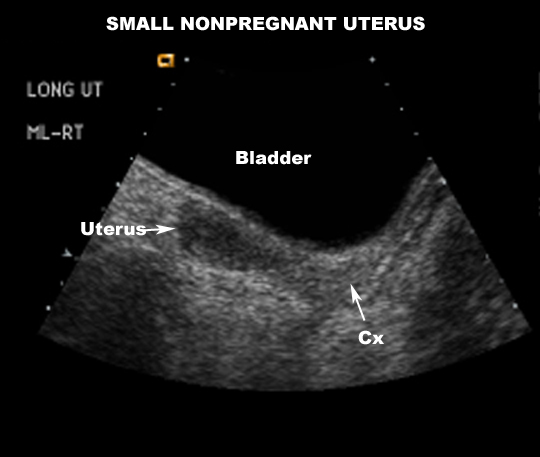

US Pelvis |